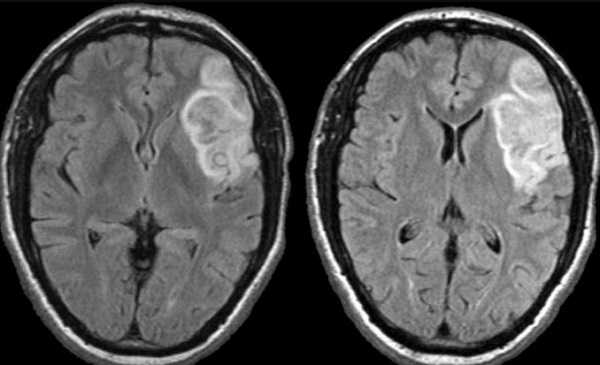

Красным выделен участок ишемии мозга в динамике на МРТ

Ишемический инсульт (МР-сканирование)

Очаги ишемии головного мозга на МРТ

Нарушение кровотока в артериальном бассейне или незамкнутом Виллизиевом круге может сопровождаться формированием обширного участка ишемии. Зона повреждения на МРТ головы будет неправильной формы с нечеткими границами из-за отека. Поражение артерий мелкого калибра выглядит как лакунарный инфаркт (округлая локализованная область изменений).